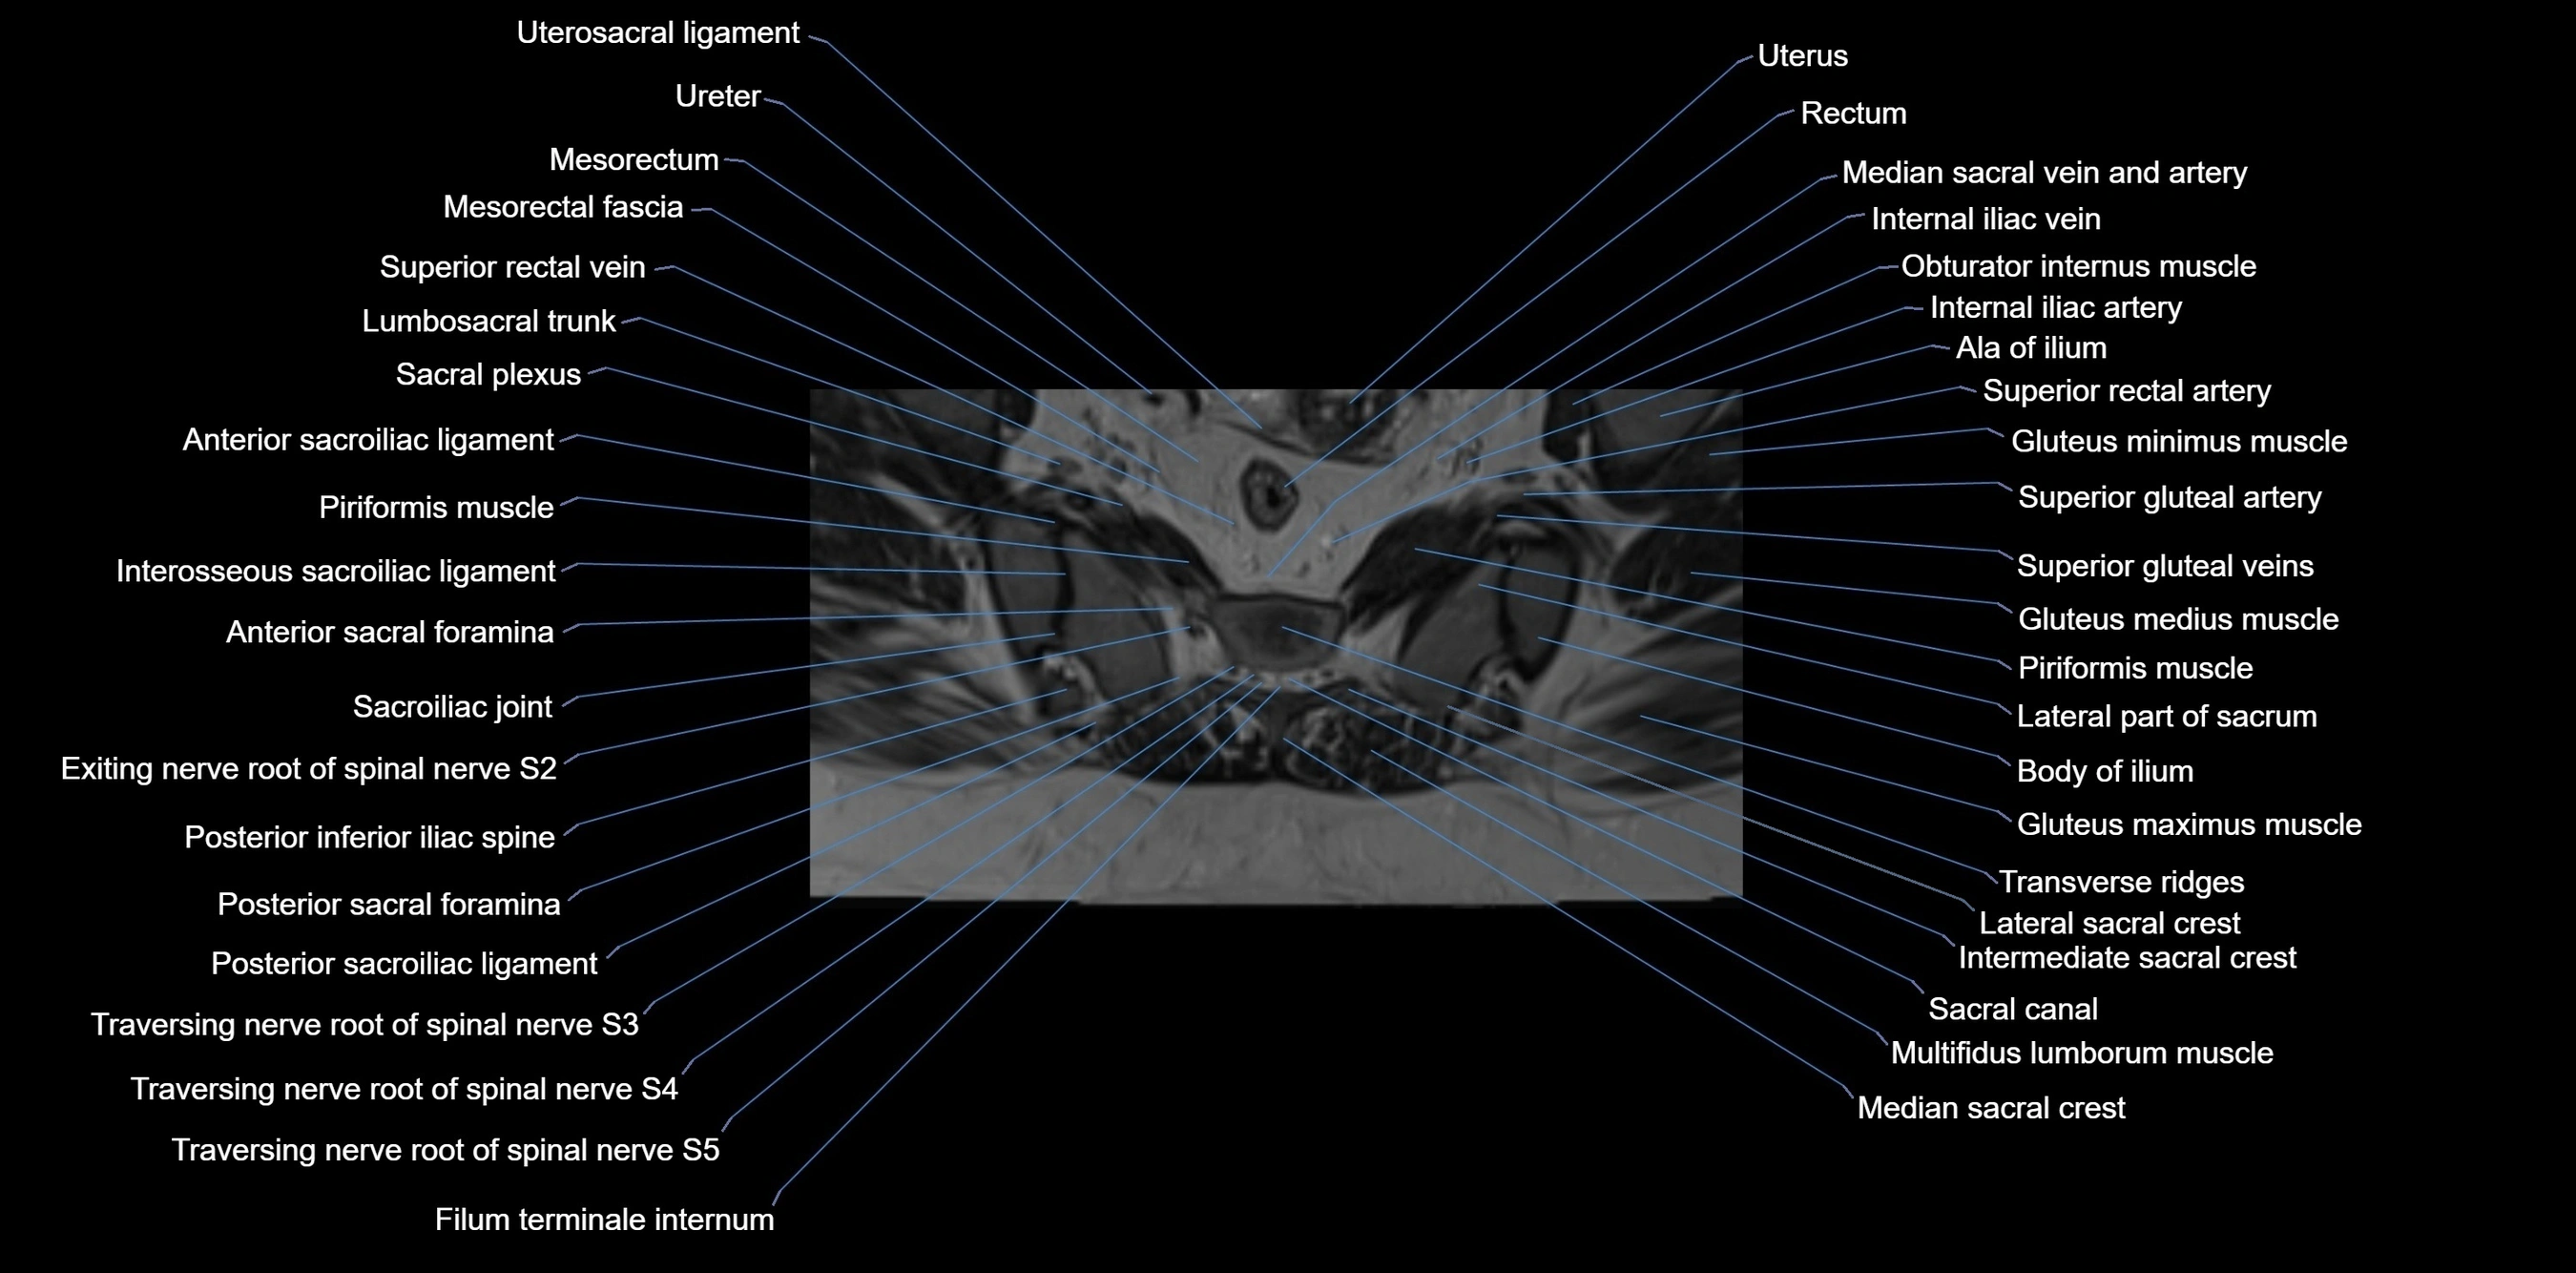

MRI image

image